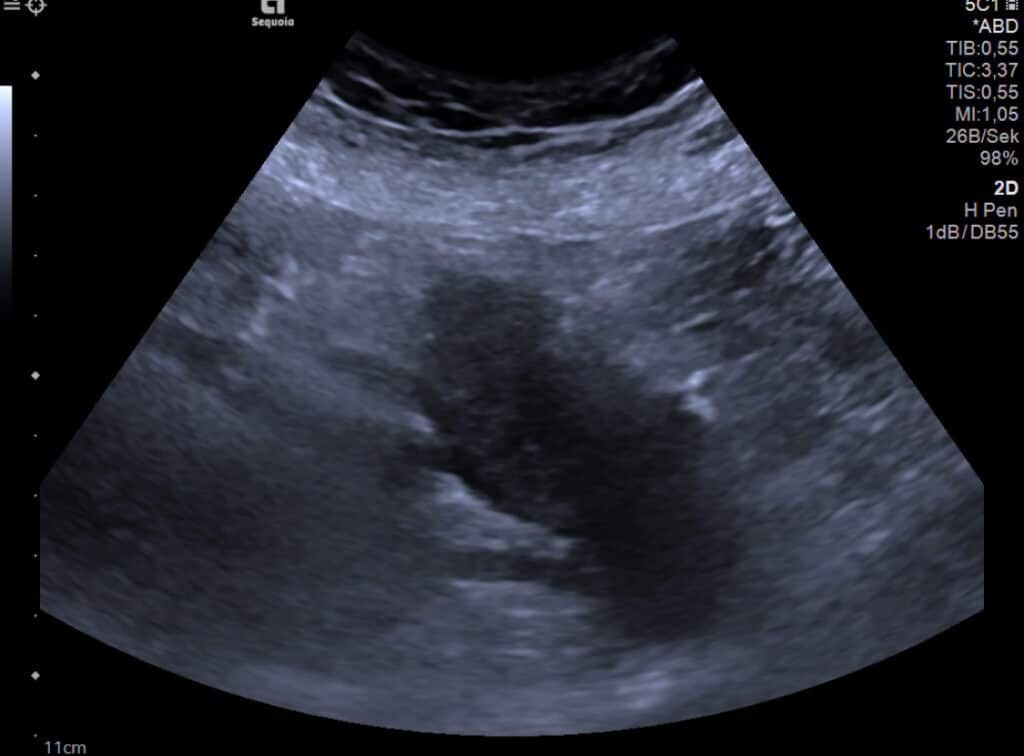

MR-morphologisch wurde der V. a. ein Pankreasschwanzkarzinom geäußert, abdomensonographisch bestätigte sich die Darstellung einer großen echoarmen Raumforderung im Pankreasschwanz. Diese erschien nach Kontrastmittel-Gabe hyperkontrastiert, was eher gegen ein duktales Pankreaskarzinom sprach.

Endosonographisch ergab sich das Bild einer segmental chronischen Pankreatitis im Schwanzbereich mit vergrößerten Lymphknoten parapankrean – eine solide Raumforderung war nicht darstellbar.

Wir entschieden uns für die sonographisch-gestützte Punktion der Pankreasraumforderung. Histologisch ergab sich eine chronisch-sklerosierende Entzündung unter Einschluss von Plasmazellen, partiell mit IgG4-Immunphänotyp, Karzinomzellen wurden nicht beschrieben.

Es wurde die Diagnose einer autoimmunen Pankreatitis Typ 1 gestellt und wir begannen die Therapie mit Prednisolon. In den sonographischen Verlaufskontrollen nach 6 Wochen und 9 Monaten stellte sich das Pankreasparenchym unauffällig dar, die Patientin war beschwerdefrei.